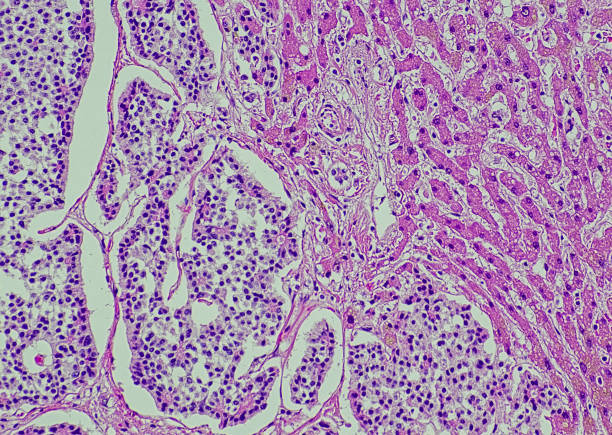

간암 초기증상 알아보기

간은 우리 몸에서 해독작용을 관장하기 때문에 우리 몸에서 중요도로 따지면 상당히 중요한 기관 중의 하나입니다. 하지만 모든 암이 그렇듯 반드시 특정한 요인으로 생기는 암은 아니지만 간암의 경우 비만, 당뇨, 흡연, 유전 등 여러 요인으로 발병할 수 있는데 정확하게 이거다라고 이야기할 수준은 아닙니다. 하지만 모든 암이 그렇듯 발전된 의학기술로 초기에 확인하면 완치할 확률도 훨씬 높게 올라가기 때문에 가능한 간암으로 발생하는 초기 증상을 확인하시어 빠른 대응이 가능하도록 하시기 바라며 이번 시간에는 간암 초기증상에 대해 알아보겠습니다.